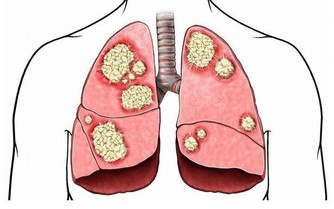

靈芝能促進肝臟對藥物、毒物的代謝,對於中毒性肝炎、肝硬化、肝功能障礙等有確切的療效。

尤其是慢性肝炎,

靈芝可明顯消除頭暈、乏力、噁心、肝區不適等症狀,並可有效地改善肝功能,使各項指標趨於正常。